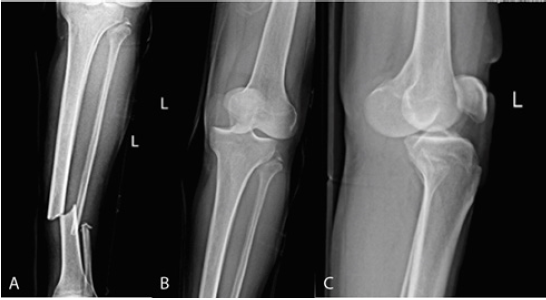

Radiographies revealed an anterior dislocation of the knee, a spiral-oblique fracture through the one-third mid-distal diaphysis of the tibia and fibula, and an avulsion fracture of the fibula (Figure 1). A closed reduction of dislocation was performed under sedation in operation room, and neurovascular examinations were rechecked. Then the limb was immobilized with a splint.

Figure 1: Initial radiographs showing the dislocated knee with simultaneous fracture of the tibial shaft. (A) Tibial shaft fracture. (B) Anterior dislocation of the knee combined with LCL and PFL avulsion. (C) Anterior dislocation of the knee.